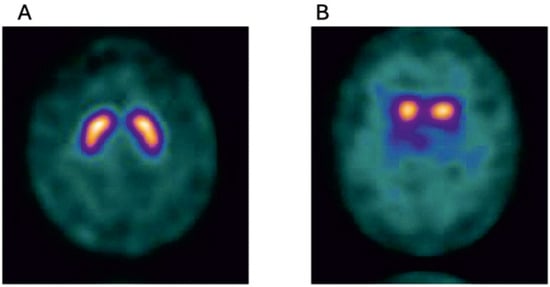

Figure 3.

Normal I 123 ioflupane SPECT image (DAT scan) (A), and for comparison an abnormal 123 ioflupane SPECT image from a participant of the Parkinsonism Incidence in North-East Scotland (PINE) study (B), showing lack of tracer uptake in the putamen bilaterally(Golden) (Courtesy—Alison D. Murray, University of Aberdeen).